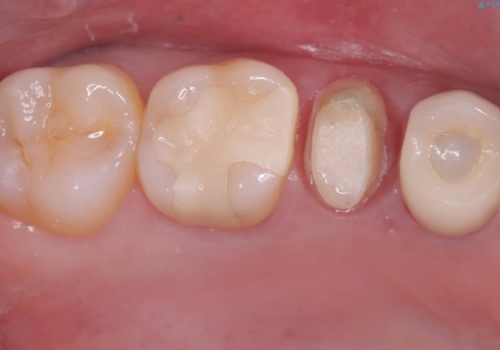

- 主訴:銀の詰め物を入れている歯が割れてしまった。

右上5番に保険適応のインレーが入っている歯がインレーを境に2つに割れてしまっていました。

露出した歯質には深いう蝕があり、一部神経を除去するもしくは全て神経を除去する可能性を説明し残存歯質量と破折リスクの観点からセラミッククラウンでの補綴修復しました。